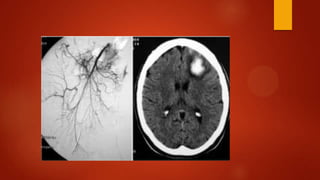

Angiografía Convencional

 Gold Standard

1. No sólo confirma el diagnóstico, sino que

permite establecer su etiología.

2. Permite distinguir entre formas oclusivas y

no oclusivas. Ello es importante porque la

IMNO puede beneficiarse de un

tratamiento conservador.

3. Permite la infusión de drogas

vasodilatadoras, como la papaverina, y

también de agentes trombolíticos.

4. Proporciona un mapa quirúrgico idóneo

para cualquier procedimiento de

revascularización.

 Confirmación diagnóstica y terapéutica

Contraindicaciones : peritonitis e

inestabilidad hemodinámica